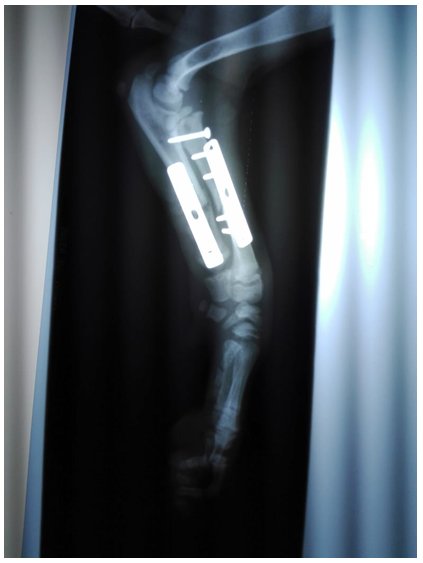

| Figura 5 Aplicación de placas de osteosíntesis DCP de largo 40mm altura 0.2mm y ancho 0.7mm y tornillos corticales convencionales de 2.00*10mm y 1 tornillo corticales de 2.00*12mm |

Resultados

El paciente llego a HOVET Hospital de Pequeños Animales con una claudicación marcada en la extremidad anterior derecha, con déficit de uso del antebrazo y dolor a la manipulación debido a un atropello de una motocicleta, el diagnóstico por imágenes una radiografía de vista lateral y dorsal del antebrazo fue significativo en la resolución del presente caso, y la resolución quirúrgica del uso de 2 DCP y 9 tornillos corticales, frente a una fractura abierta de primer grado del cubito, y la fractura completa de radio a nivel distal y proximal, no se reportó complicaciones intraquirúrgicas en el procedimiento, es importante considerar que este tipo de fracturas es poco común y una resolución pronta da respuestas positivas en la recuperación del paciente.

Figura 6 Radiografía vista latero lateral, post quirúrgico

Figura 7 Radiografía vista dorso ventral, post quirúrgico